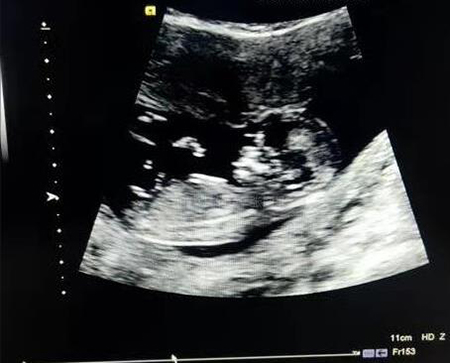

二维是平面成像;三维是在二维的基础上,通过计算机技术,增加了三维成像功能,形成胎儿的立体图片;四维则是在三维的基础上,在图像上增加了时间维度,形成胎儿的连续性图片,类似于短动图。简单来说,二维是平面照片、三维是立体照片,四维是动图,不管是三维、还是四维,都是通过计算机的作用,将二维图像进行合成处理得到的复合图像。

仅仅通过二维成像超声检查,大部分胎儿畸形是不能筛查出来的,如胎儿心脏、胎儿腹腔脏器等畸形。二维超声是把胎儿图像分层,从里到外、不同切面、不同角度的观察胎儿的颅脑、四肢、各个器官脏器及胎儿附属物,这些优势是三维、四维超声做不到的,因此孕妈们来医院做的超声检查大多数是二维检查,但如果二维发现胎儿有异常,可再使用三维、四维成像,提供多一些信息,例如二维超声发现胎儿唇裂,可进一步使用三维成像辅助诊断,也有利于孕妈及家属比较直观看懂胎儿的异常。此外,三维、四维的优势还在于情感优势,孕妈和家属比较容易辨认,能看出宝宝的五官、甚至是在宫腔里活动、玩脐带的小动作,是宝宝人生的第一张照片;而二维超声,只有超声专业人士才看得懂。

三维、四维超声也并不比二维图像清晰,二维图像是否清晰,却决定三维、四维图像清晰与。也不存在三维比四维更清晰,从排除胎儿畸形角度来说,四维能达到的效果和三维没有什么不同,优势也和三维相仿。

(超声二维图像)